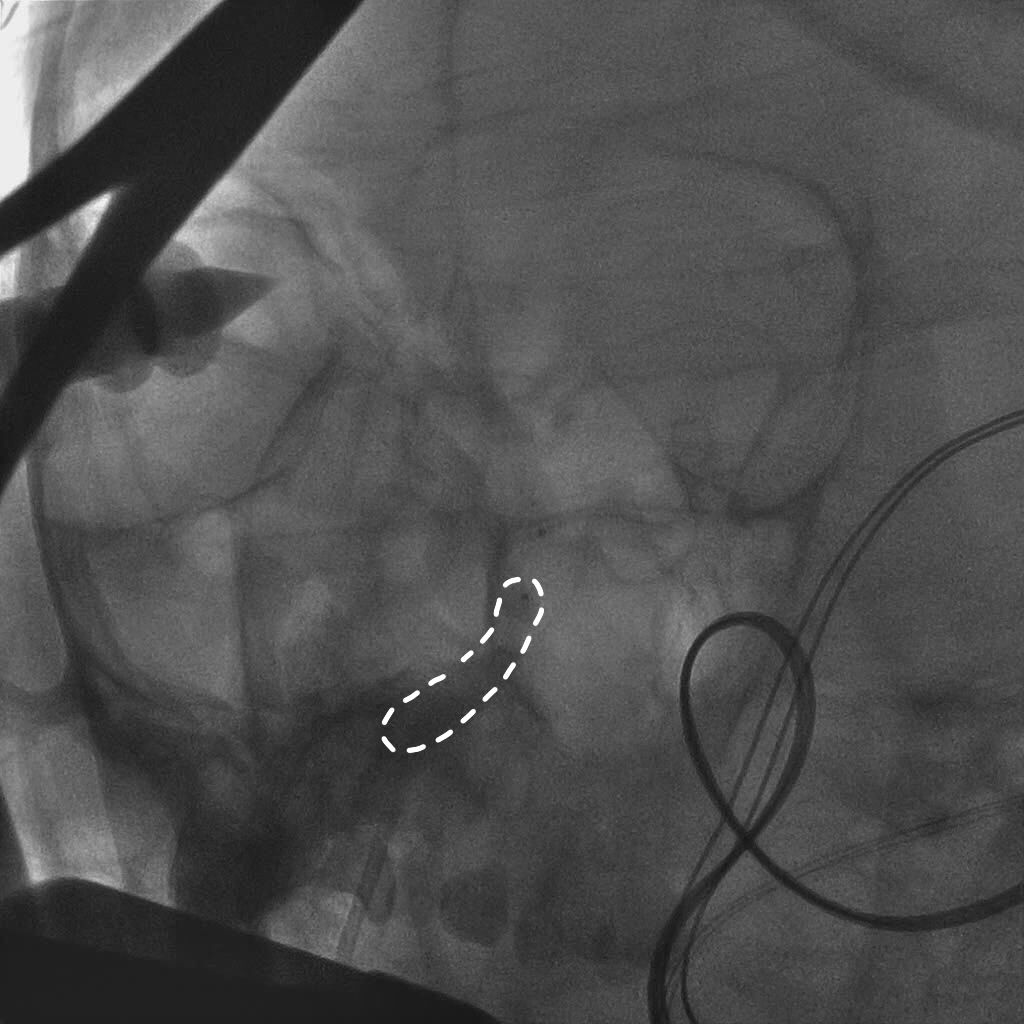

全身肝素化后,路图下将6FGuiding导引导管放置于右侧颈内动脉岩谷水平段,使用Scepter球囊微导管在014微导丝带领下超选进入颈内动脉岩谷垂直段,充盈球囊,造影显示阻断颈内动脉满意后继续手术。

球囊到位

球囊充盈,虚线为球囊